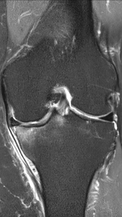

Рецидивирующий синовит коленного сустава

Излечение за 1 процедуру ФДТ Ревиксан

Параметры изменяются в зависимости от процедуры

Дата публикации: 17.11.2025 11:26:14